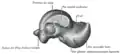

Left talus, medial surface -

Left talus, lateral surface